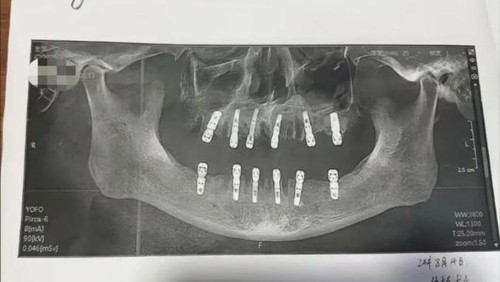

Anak Huang, Shu, melaporkan kasus ini setelah menemukan bukti ayahnya telah menandatangani persetujuan untuk pencabutan 23 gigi dan pemasangan 12 gigi baru. Prosedur yang dilakukan termasuk pembuatan lubang di tengkorak dan rahang bawah, yang dikenal dengan istilah 'immediate restoration' atau 'restorasi segera.'